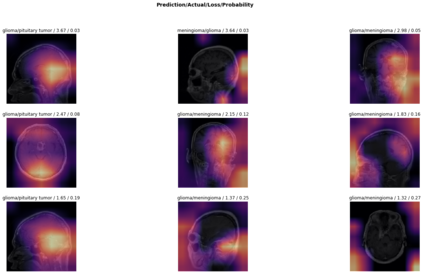

Magnetic Resonance Imaging (MRI) is a principal diagnostic approach used in the field of radiology to create images of the anatomical and physiological structure of patients. MRI is the prevalent medical imaging practice to find abnormalities in soft tissues. Traditionally they are analyzed by a radiologist to detect abnormalities in soft tissues, especially the brain. The process of interpreting a massive volume of patient's MRI is laborious. Hence, the use of Machine Learning methodologies can aid in detecting abnormalities in soft tissues with considerable accuracy. In this research, we have curated a novel dataset and developed a framework that uses Deep Transfer Learning to perform a multi-classification of tumors in the brain MRI images. In this paper, we adopted the Deep Residual Convolutional Neural Network (ResNet50) architecture for the experiments along with discriminative learning techniques to train the model. Using the novel dataset and two publicly available MRI brain datasets, this proposed approach attained a classification accuracy of 86.40% on the curated dataset, 93.80% on the Harvard Whole Brain Atlas dataset, and 97.05% accuracy on the School of Biomedical Engineering dataset. Results of our experiments significantly demonstrate our proposed framework for transfer learning is a potential and effective method for brain tumor multi-classification tasks.